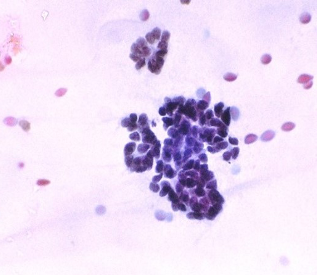

Figs 1 and 2 from a mass in the right hypochondriac region.

Make your diagnosis.

Fig 1 : Giemsa x 100

Fig 2 : Giemsa x 400

Highly suggestive of papillary adeno-carcinoma Endometrium - Shows adequate cellularity with papillae of carcinoma cells showing hyperchromatic and pleomorphic nuclei, highly suggestive of papillary adenocarcinoma of the endometrium.